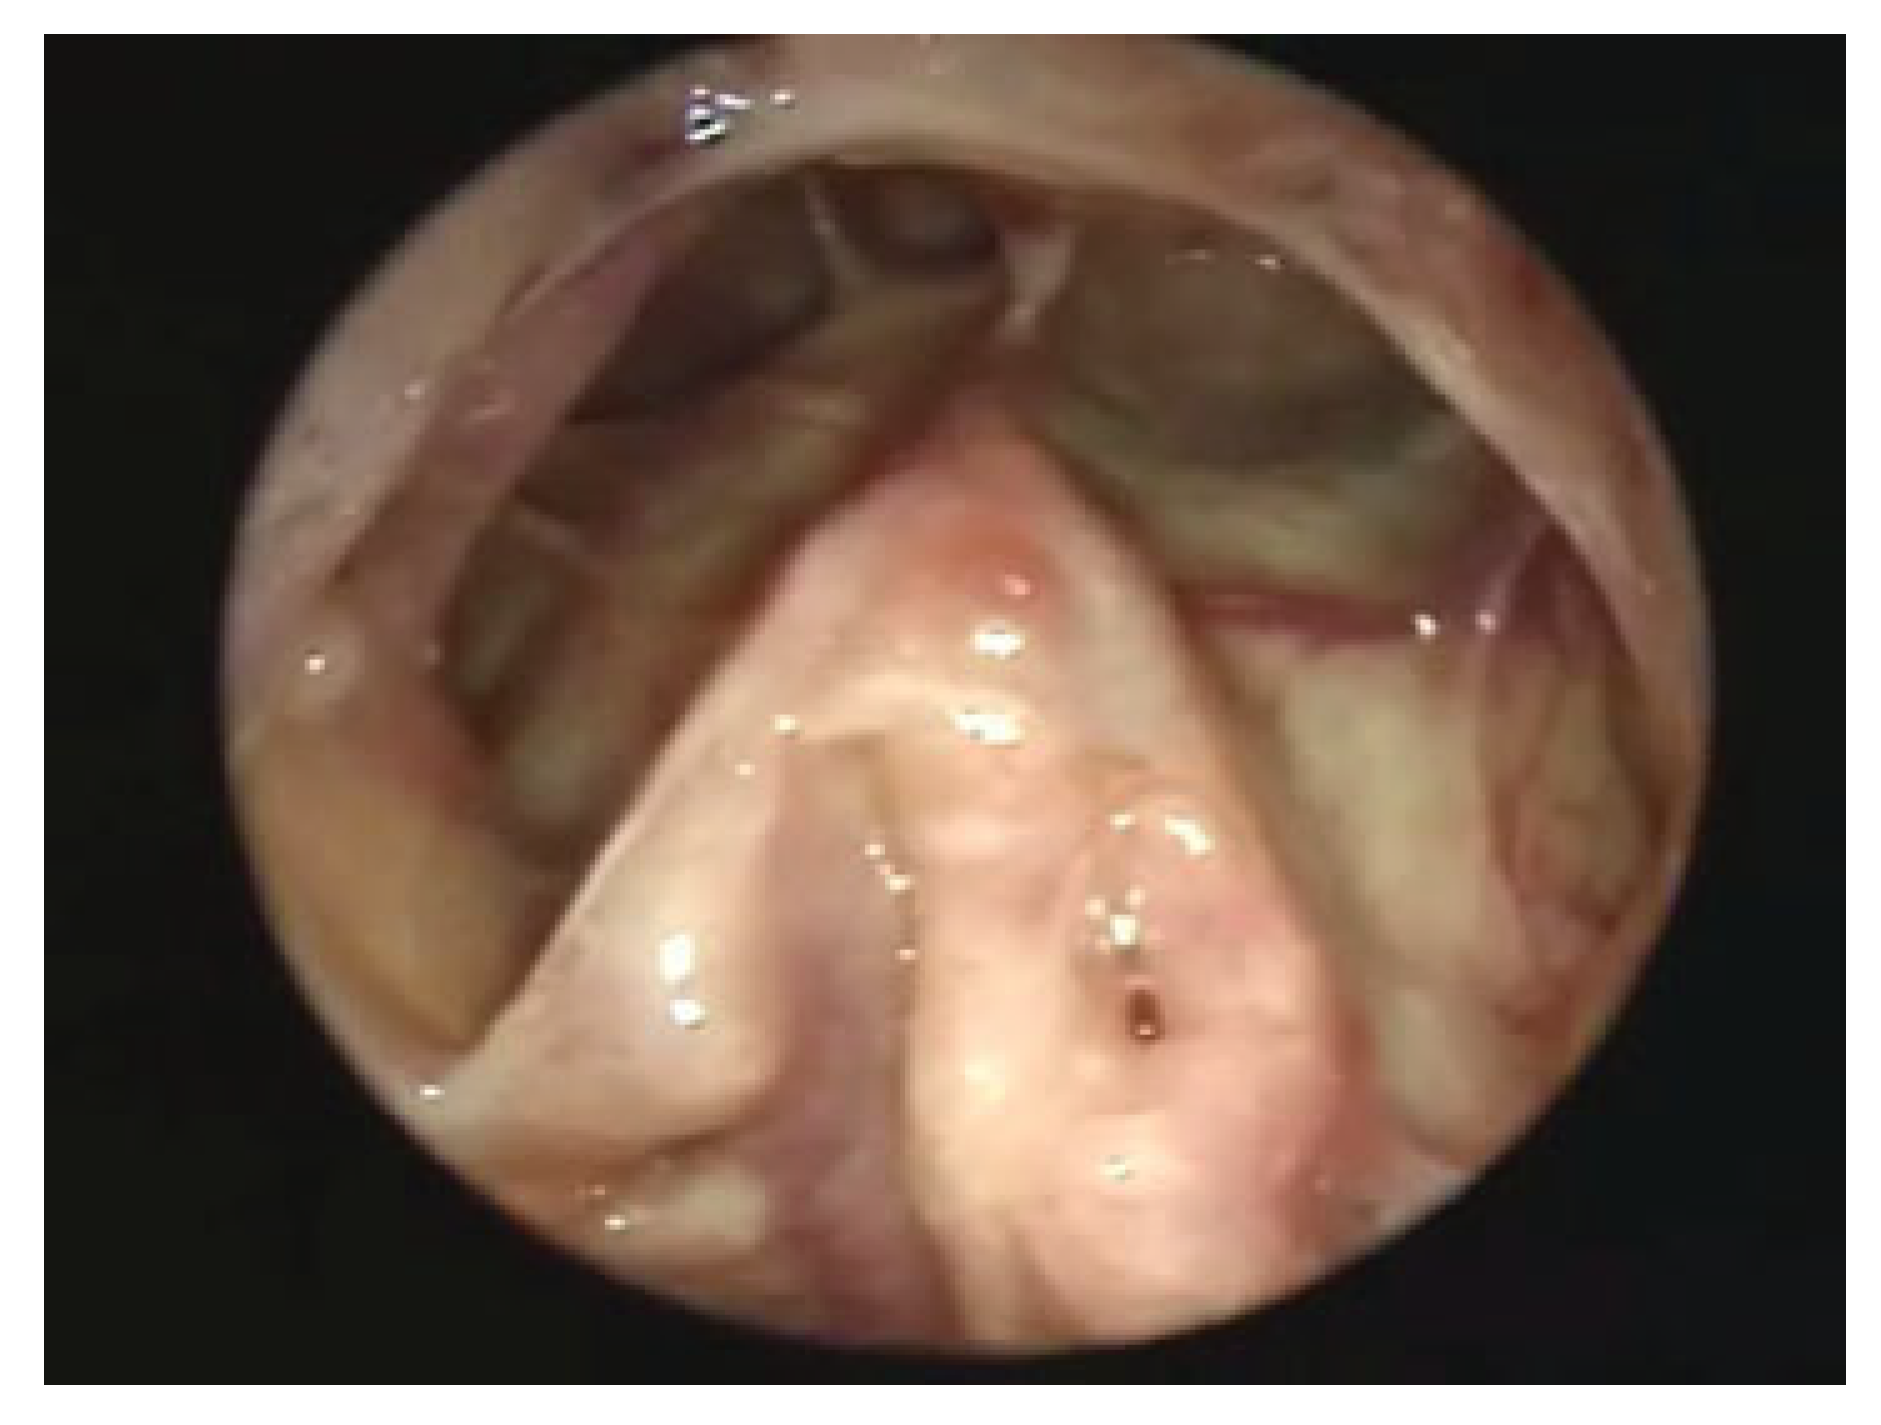

Figure 4.

Healed endoscopic view after an endoscopic modified Lothrop procedure.